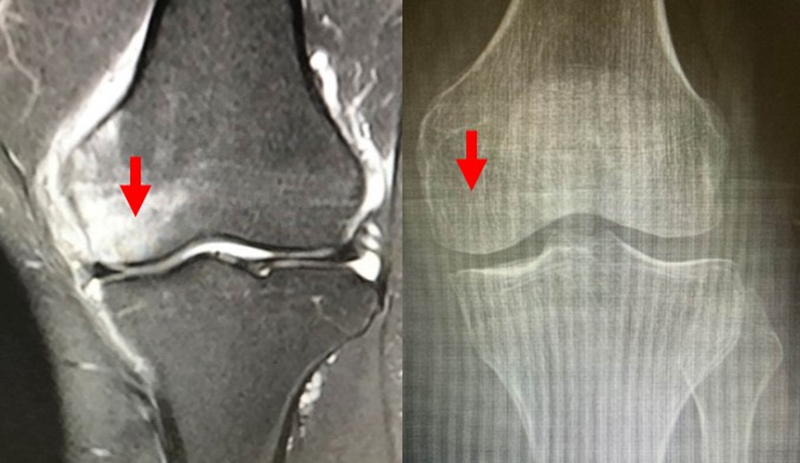

a.患者,59岁女性,AP侧位片显示SONKⅠ期,FTA<180°;b.MRI T2显示病变深度<20mm,患者出现症状1年后保守治疗;c.75岁女性,X线显示SONKⅠ期,FTA>180°;d. MRI T2显示病变深度>20mm,患者于症状出现后11周行手术治疗

影响保守治疗效果的因素